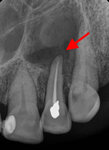

Periapical radiograph showing large periapical radiolucency related to root canal-treated lateral incisor; final pathology was consistent with a periapical cyst

From the personal collection of Melanie S. Lang and Thomas B. Dodson